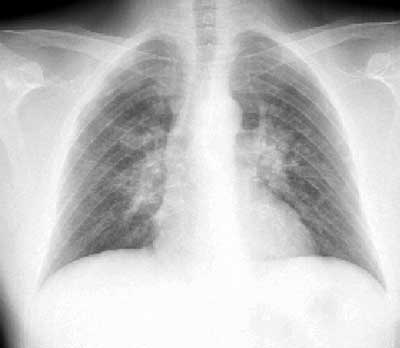

Рис. 2. Цифровая рентгенография легких на аппарате "Пульмоскан-760" (НПП "Адани", Беларусь).

Определяется увеличение бронхопульмональных лимфоузлов, интерстициальные и очаговоподобные изменения, морфологическим субстратом которых являются саркоидозные гранулемы.